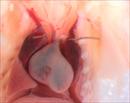

| Mutant 2459-003-1 (E14.5) is developmentally delayed. Outflow is slightly malrotated which is confirmed to be DORV and ventricular non-compaction by EFIC imaging | b2b2459Clo/b2b2459Clo | C57BL/6J-b2b2459Clo |